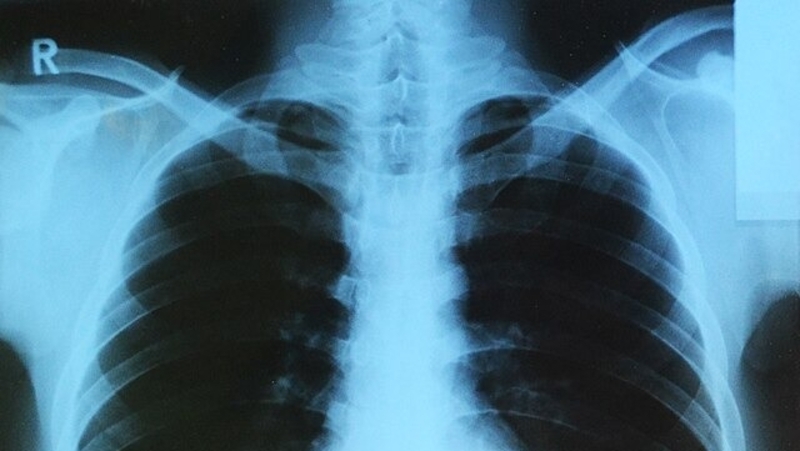

Название болезни произошло от латинского tuberculum — «бугорок». Болеют туберкулёзом люди и животные. Это инфекционное заболевание коварно — распространяется воздушно-капельным путём, а протекает бессимптомно. Болезнь вызывают разные виды микобактерий, их называют палочками Коха. Они способны жить внутри клеток организма. Чаще всего поражаются лёгкие, реже мочеполовая система, периферические лимфатические узлы, кожа, глаза, кости и суставы. Симптомы лёгочной формы туберкулёза проявляются когда болезнь прогрессирует: появляются лихорадка, длительный кашель, боль в груди, кровохарканье, потеря аппетита, ночная потливость. На сегодняшний день болезнь полностью излечима, но риск заболеть ею остаётся.

«Заболеваемость туберкулёзом в Лермонтове в 2024 году составила 12,2 на 100 тыс. взрослого населения. Это ниже среднекраевого значения 17,3. Больных детей в Лермонтове не выявлено. Заболеваемость туберкулёзом среди детей в регионе составила 1,4 на 100 тыс. населения в 2024 году. Чаще всего взрослые болеют диссеминированным туберкулёзом лёгких»,

Чтобы не заболеть туберкулёзом, стоит регулярно проводить профилактику — раз в год делать флюорографию лёгких. Детям проводят туберкулинодиагностику и ставят вакцину БЦЖ. Здоровый образ жизни также минимизирует риск. Сбалансированное питание, спорт, закаливание и отказ от вредных привычек повышают иммунитет, а значит — снижают вероятность развития болезни.